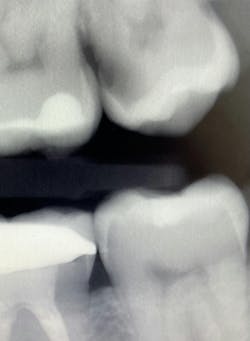

I see more complications and pathologies when using 3D tomosynthesis than I ever did with my old 2D images (figure 4). I can treat more because I can see more bone loss, interproximal caries, fractures, resorptions, abscesses, and more (figure 5).

Fortunately, 3D intraoral tomosynthesis found its way into the dental field. Based on the findings from a study out of the University of North Carolina, dentists who use 3D tomosynthesis for intraoral x-rays can detect approximately 36% more caries (figures 8 and 9).1 That’s tremendous!